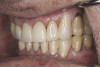

(23.) Provisionals, right lateral, closed view.

Figure 23